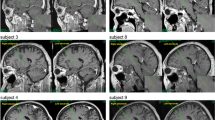

Both patients underwent bilateral Globus pallidus deep brain stimulation via a standard technique26. Medtronic 3387 DBS leads were placed in left and right posteroventral GPi. Each electrode had four circumferential 1.5 mm channels. A CT head scan was performed to assess the lead position after implantation (verified by Image Fusion with the pre-operative MRI). Approximate positions of three lead channels are displayed in supplementary Fig. 1. Internalization of DBS leads and implantation of internal pulse generators was done approximately a week after clinical testing for efficacy (Fig. 1A).

The overview of data recording and IED task. (A) two DBS leads with three recording channels were placed in the right and left GPi separately to record the LFP signal during the IED task. (B) schematic of Cantab Intra-Extra Dimension shift task. The task contains nine rule sets. In each section, when the patient completes six correct trials sequentially, the rule changes. Each rule section has 50 trials at maximum, and if the patient does not reach six consecutive correct trials within the 50 trials, the experiment ends at that rule section. (C) Graphic representation of a single trial. Each trial starts when the visual object appears on the blank screen. The patient moves to touch the screen in order to choose the preferred object. Auditory and visual feedbacks are given immediately and simultaneously to the patient upon screen touch. The red marker indicates the "incorrect" answer in the visual feedback, and the green marker indicates the "correct" answer. For auditory feedback, the patient hears "correct" for the correct answers and "incorrect" for incorrect answers. The trial ends when the screen becomes blank before the start of the next trial.